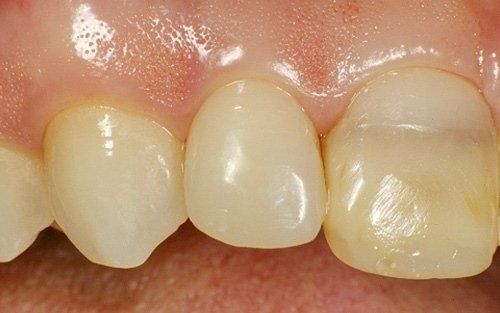

Il restauro definitivo sul dente laterale: notare la buona integrazione fra il dente e il restauro.

Il laterale di sinistra ultimato.